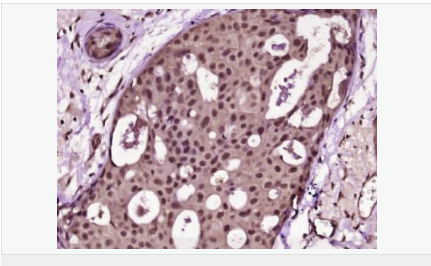

| 產(chǎn)品應用 | ELISA=1:5000-10000 IHC-P=1:100-500 IHC-F=1:100-500 Flow-Cyt=1μg/Test (石蠟切片需做抗原修復) not yet tested in other applications. optimal dilutions/concentrations should be determined by the end user. |

| 產(chǎn)品介紹 | Proliferation Marker Ki67 antigen is the prototypic cell cycle related nuclear protein, expressed by proliferating cells in all phases of the active cell cycle (G1, S, G2 and M phase). It is absent in resting (G0) cells. Ki67 antibodies are useful in establishing the cell growing fraction in neoplasms (immunohistochemically quantified by determining the number of Ki67 positive cells among the total number of resting cells = Ki67 index). In neoplastic tissues the prognostic value is comparable to the tritiated thymidine labelling index. The correlation between low Ki67 index and histologically low grade tumours is strong. Ki67 is routinely used as a neuronal marker of cell cycling and proliferation. Function: Thought to be required for maintaining cell proliferation. Subcellular Location: Nucleus. Chromosome. Predominantly localized in the G1 phase in the perinucleolar region, in the later phases it is also detected throughout the nuclear interior, being predominantly localized in the nuclear matrix. In mitosis, it is present on all chromosomes. Similarity: Contains 1 FHA domain. SWISS: P46013 Gene ID: 4288 Database links: Entrez Gene: 4288 Human Entrez Gene: 17345 Mouse Omim: 176741 Human SwissProt: P46013 Human SwissProt: Q91VE6 Mouse Unigene: 689823 Human Unigene: 80976 Human Unigene: 4078 Mouse Unigene: 233802 Rat Important Note: This product as supplied is intended for research use only, not for use in human, therapeutic or diagnostic applications. 細胞增殖標志物(Proliferation Marker) Ki67與PCNA一樣,為細胞增殖的一種標記,在細胞凋亡中S、G2 、M期均有表達,G0期缺如。 Ki-67增殖指數(shù)高低與許多腫瘤的分化程度、浸潤、轉移以及預后密切相關,因此被廣泛作為各種惡性腫瘤的必檢項目之一。 |